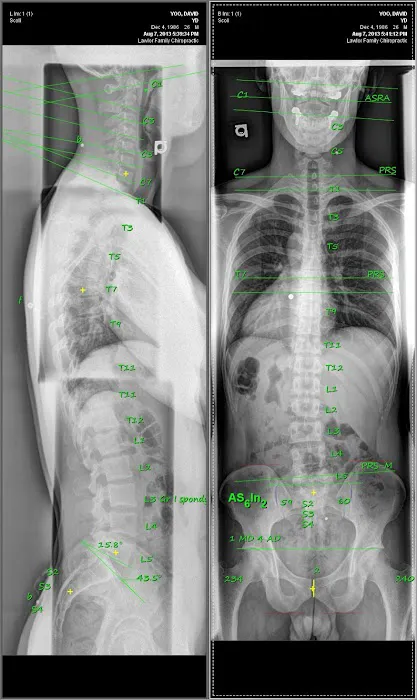

The philosophy at NJ Gonstead Chiropractic is centered on the Gonstead method, a specific and highly detailed approach to chiropractic care. This technique involves a thorough analysis of the spine to locate the precise cause of a patient's issue, rather than using a general adjustment. As a satisfied customer noted, "Dr. Yoo took the time to listen to my concerns and clearly explained the treatment plan using the X-ray." This highlights the practice's commitment to a detailed diagnostic process, ensuring that treatments are targeted and effective. The Gonstead technique is known for its precision, which often leads to "significant relief from pain and noticeable improvements in my posture, flexibility, and overall well-being," as one patient experienced. Dr. Yoo's dedication to this specific methodology and his patient-centered approach are what define the practice and set it apart as a leader in local chiropractic care.

- Patient Education: A key part of the service is Dr. Yoo's commitment to explaining the patient's condition, the X-ray findings, and the treatment plan in a clear and understandable manner. This empowers the patient to be an active participant in their recovery.

Feb 10, 2020 · Eddie R. BarriosI have been treated by nearly 15 chiropractors over the last 35 years, and 1 or 2 have provided temporary relief. They also didn't take the time to thoroughly examine me, and only 1 had taken x-rays.I rolled the dice and contacted Dr. Yoo, in hopes that a Gonstead practitioner would be more thorough and helpful.Dr. Yoo took the time to X-ray my spine, explained how bad it looks, and with his treatments, has provided significantly more relief than my previous 15 chiropractors.My advice to anyone who has headaches, dizziness, neck/back pain or just restricted range of motion, MAKE THE CALL & GET ADJUSTED. There is no long term contract & getting adjusted does not hurt!Hopefully, with continued, routine visits, I can look forward to a less painful future!